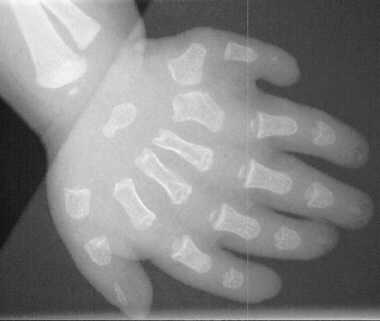

A 6 month old Amish infant female was referred for symmetric polydactyly of both hands. Prior to her presentation in our clinic she was seen and evaluated by a cardiologist for an apparent congenital heart murmur. On physical examination of the upper extremities there was a sixth digit on the ulnar border of both hands. The finger nails appeared to be dysplastic.

The types of tissues involved in this disorder, are the long bones of the skeleton, nails, and teeth.

On x-ray the distal and middle phalangeal segments are shorter in relation to the proximal phalangeal segments.